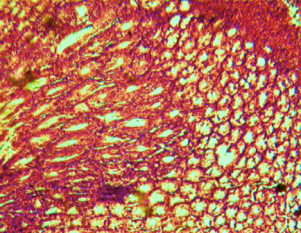

Histological evaluation of gastric lesion

Histological observation showed extensive damage of the gastric mucosa in the ulcer negative control group with necrotic lesions penetrating deeply into the mucosa accompanied by extensive edema and leucocyte infiltration of the submucosal layer (group 2).

Rats that received treatment with aqueous and methanol extracts of the leaves of D. thollonii had comparatively better protection of the gastric mucosa as seen by the reduction of ulcer area, reduced submucosal edema and leucocytes infiltration after 14 days of treatment (fig. 4).

Fig. 4: Histological study of acetic acid-induced gastric damage in rats

In fig. 4: (a’): histological section of a normal control rat: no injuries to the gastric mucosa are seen and the gastric wall is normal. ((b’): histological section of an ulcer negative control rat: there is severe destruction of the surface epithelium and necrotic lesions penetrating deeply into mucosa and submucosa layer. (c’): histological section of rats treated with Maalox (50 mg/kg): the gastric wall appears normally, but there is edema of mucosa and sub mucosa layer.(d’): the histological section of rats treated with Ranitidine (50 mg/kg): the gastric wall appears normally with all layers. (e’): the histological section of rats treated with 125 mg/kg of aqueous extract: there is mild disruption of the sub mucosal layer. (f’): histological section of rats treated with 250 mg/kg aqueous extract: there is moderate disruption of the surface epithelium. (g’): histological section of rats treated with 500 mg/kg of aqueous extract: there is mild disruption of the sub mucosal layer and edema of the muscle. (h’): histological section of rats treated with 125 mg/kg of methanol extracts: there is mild disruption of the epithelium surface and the sub mucosal layer and edema of the serosal layer. (i’): histological section of rats treated with 250 mg/kg of methanol extract: there is mild disruption of the epithelium surface and edema of the submucosal and serosal layers. (j’): histological section of rats treated with 500 mg/kg of methanol extract: there is moderate disruption of the epithelial surface although the gastric wall appears normally.